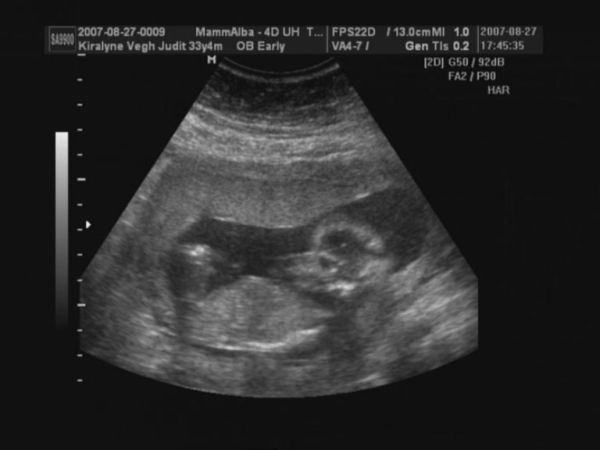

Megjöttünk 4D-ről.

CRL 9,54

BPD 2,83

A gép 14+6 napra dobta ki a korát, ami jó is.

Pulzus 167 percenként

Jelenleg kuki nem látható. Szóval remény még mindig van.

alsónézet, itt kellene lennie a kukinak.

A feneke és a lábacskái látszanak.

2D oldalról